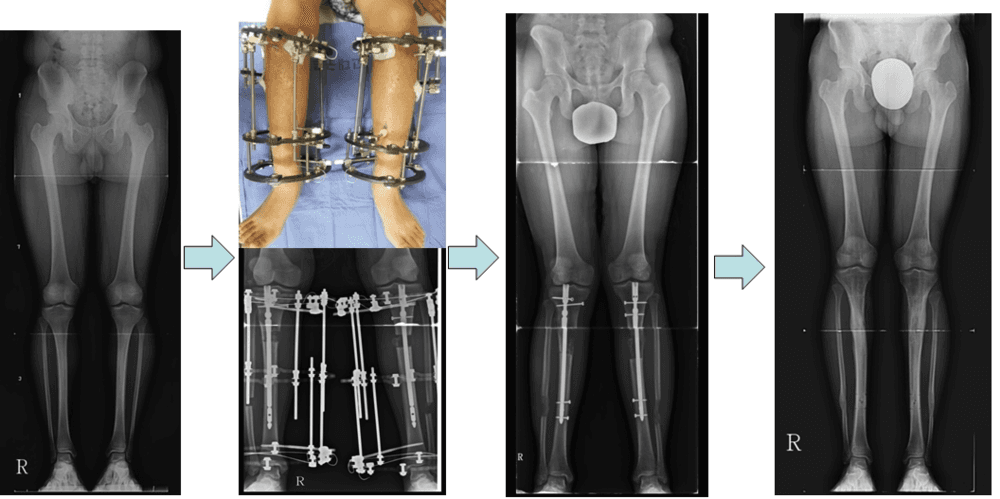

Lower Limb Lengthening in Achondroplasia Patient